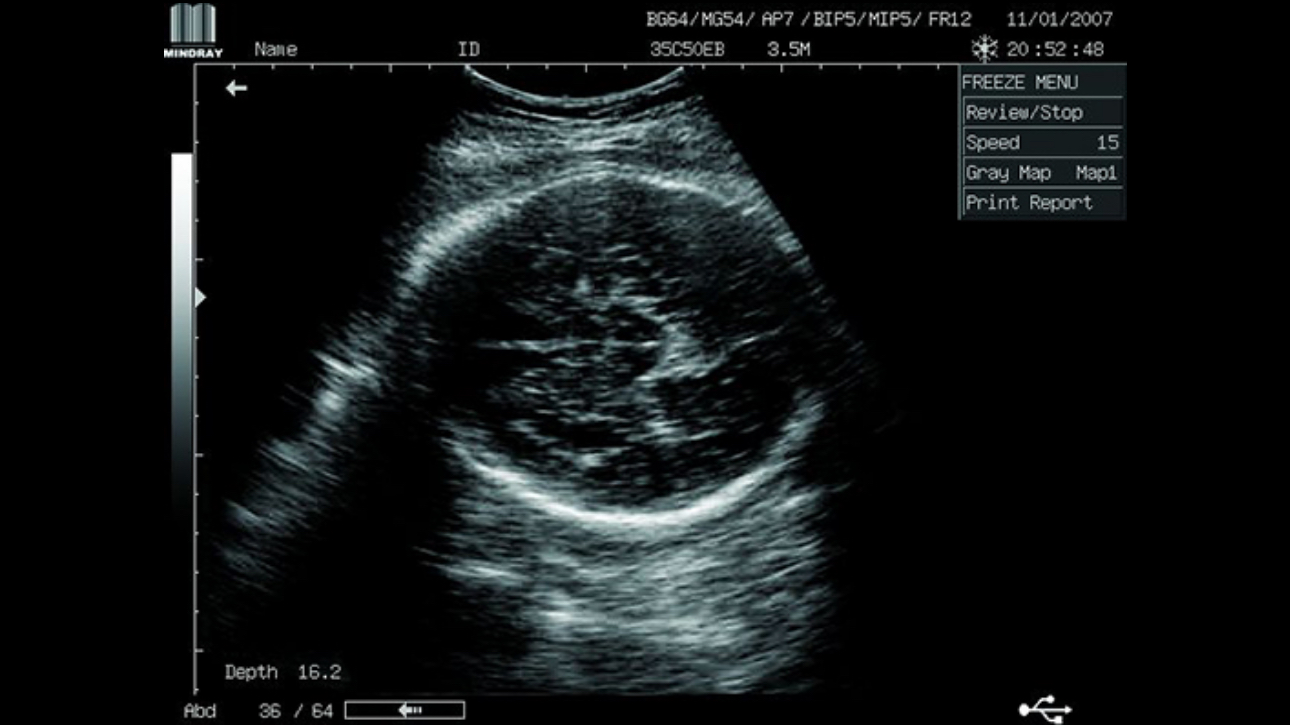

Clinical Images